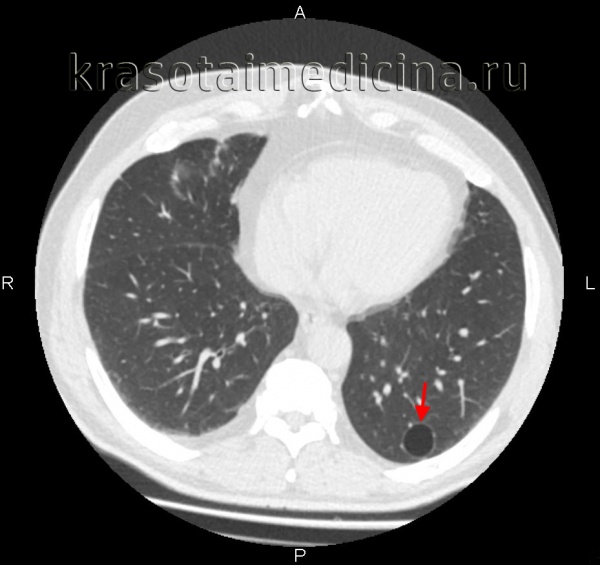

Буллезная эмфизема легкого – это локальные изменения легочной ткани, характеризующиеся деструкцией альвеолярных перегородок и формированием воздушных кист диаметром более 1 см (булл). При неосложненном течении буллезной эмфиземы легких симптомы могут отсутствовать вплоть до возникновения спонтанного пневмоторакса. Диагностическое подтверждение буллезной эмфиземы легких достигается с помощью рентгенографии, КТ высокого разрешения, сцинтиграфии, торакоскопии. При бессимптомной форме возможно динамическое наблюдение; в случае прогрессирующего или осложненного течения буллезной болезни легких проводится хирургическое лечение (буллэктомия, сегментэктомия, лобэктомия).

Буллезная эмфизема легкого – ограниченная эмфизема, морфологическую основу которой составляют воздушные полости (буллы) в паренхиме легкого. В зарубежной пульмонологии принято различать блебы (англ. «blebs» - пузыри) - воздушные полости размером менее 1 см, расположенные в интерстиции и субплеврально, и буллы - воздушные образования диаметром более 1 см, стенки которых выстланы альвеолярным эпителием. Точная распространенность буллезной эмфиземы легкого не определена, однако известно, что данное заболевание служит причиной спонтанного пневмоторакса в 70–80% случаев. В литературе буллезную эмфизему легких можно встретить под названиями «буллезная болезнь», «буллезное легкое», «ложная/альвеолярная киста», «синдром исчезающего легкого» и др.

Кроме этого, буллы могут быть солитарными и множественными, одно– и двусторонними, напряженными и ненапряженными. По распространенности в легком дифференцируют локализованную (в пределах 1-2-х сегментов) и генерализованную (с поражением более 2-х сегментов) буллезную эмфизему. В зависимости от размера буллы могут быть мелкими (диаметром до 1 см), средними (1-5 см), крупными (5-10 см) и гигантскими (10-15 см в диаметре). Буллы могут располагаться как в неизмененном легком, так и в легких, пораженных диффузной эмфиземой.

Диагностика буллезной эмфиземы легких основывается на клинических, функциональных и рентгенологических данных. Курация больного осуществляется пульмонологом, а при развитии осложнений – торакальным хирургом. Рентгенография легких не всегда эффективна в выявлении буллезной эмфиземы легких. В то же время, возможности лучевой диагностики существенно расширяет внедрение в практику КТ высокого разрешения. На томограммах буллы определяются как тонкостенные полости с четкими и ровными контурами. При сомнительном диагнозе удостовериться в наличии булл позволяет диагностическая торакоскопия.